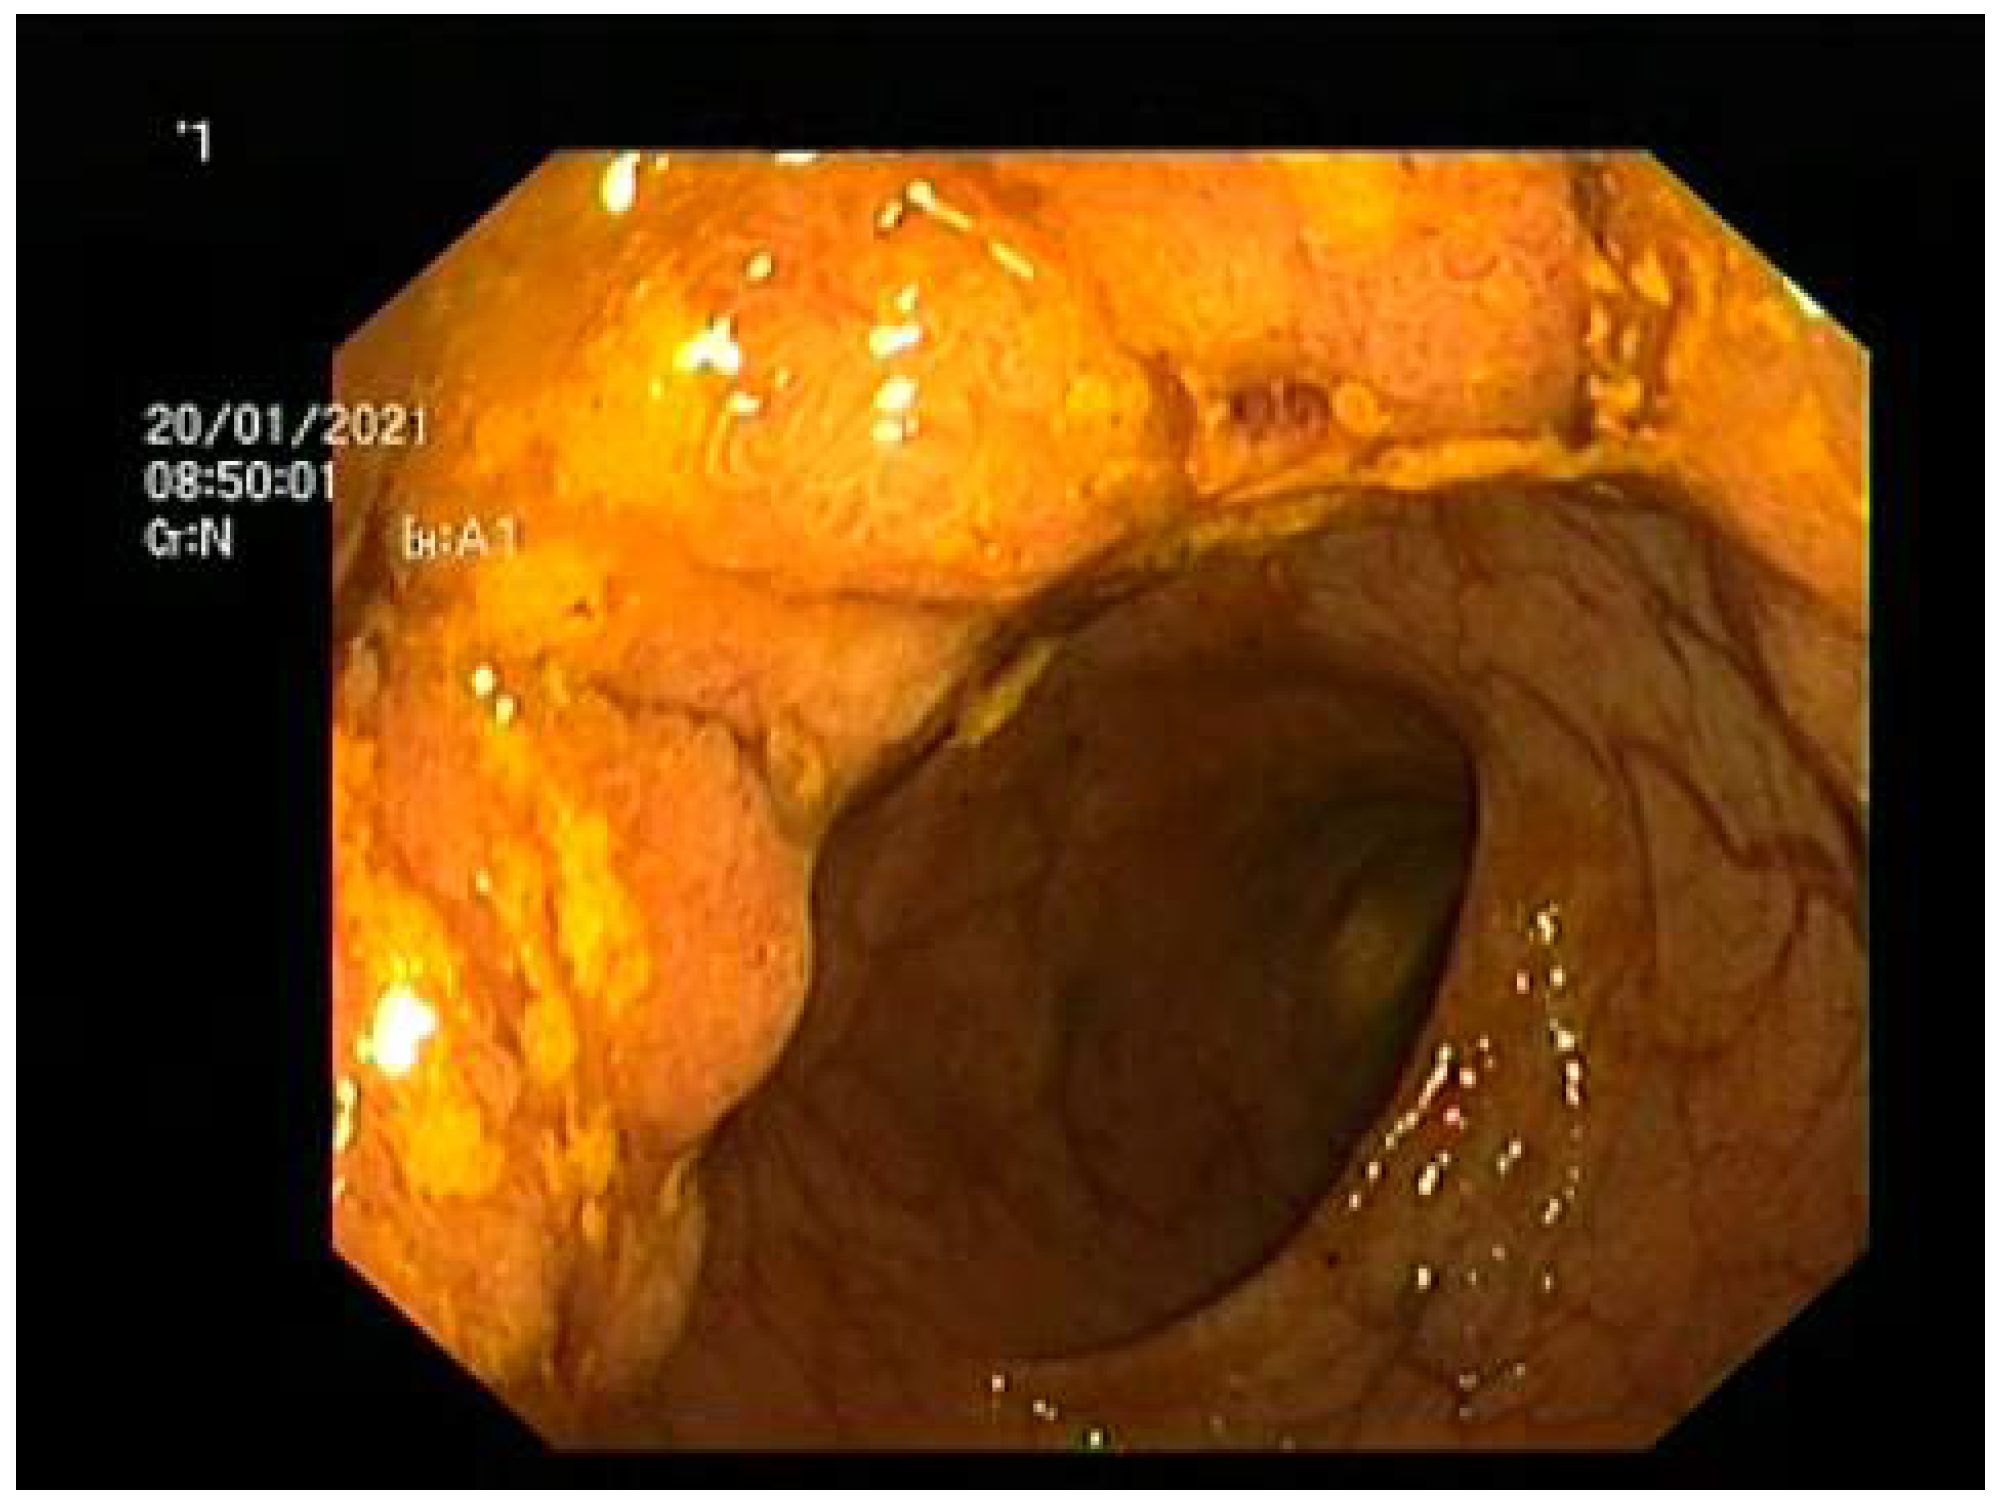

Considering the patient’s profuse diarrhea with 10–12 watery or mucous stools/24 h (Figure 1), a colonoscopy was performed. The examination revealed 12 cm length circumferential lesion located at 8 cm from the anal verge (Figure 2). Histology revealed tubulo-villous adenoma with low-grade dysplasia. Another villous adenoma measuring 2/2 cm was identified on the descending colon, before the splenic flexure, histology revealing tubulo-villous adenoma with high-grade dysplasia. In addition, a semi-pedunculated polyp, 1 cm in diameter (Isp on Paris classification), was found on the right colon, 4 cm from the ileocecal valve.

Figure 2.

Tumoral mass identified at colonoscopy.